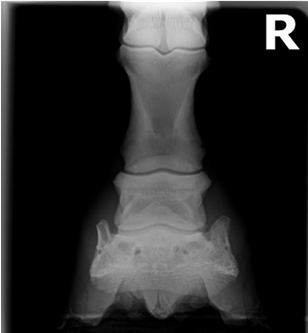

• what view is this?

dorsoproximal Palmarodistal 60o oblique (upright navicular)